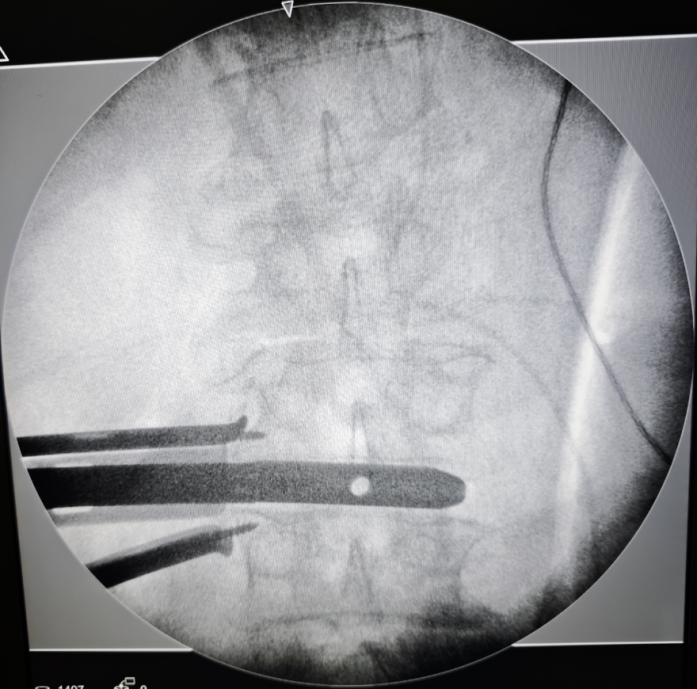

術中(zhong)影(ying)像

確(que)認(ren)透視節段